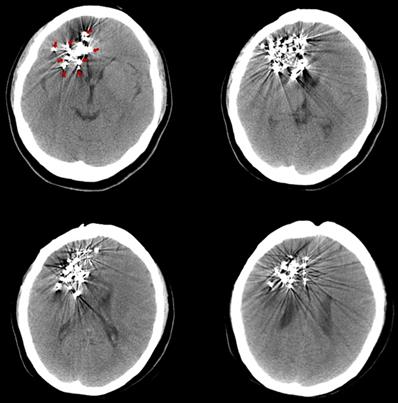

The pre-125I implantation plan was performed with the computerized treatment planning system (TPS, Beijing Astro Technology Ltd., Co., Beijing, China). With a negative pressure vacuum pad, the patients were fixed on the CT scan bed. After anesthetization with 2% lidocaine, an incision of approximately 2 mm was made on the scalp. Then, 2-4 mm diameter holes on the skull were made with an electric cranial drill. Flat needles were inserted into the tumor, and the angle and depth of the needle were dynamically adjusted under CT guidance. Iodine-125 seeds (diameter of 0.8 mm, length of 4.5 mm, half-life of 59.4 days; Model 7711, Beijing Atom and High Technique Industries, Inc., Beijing, China) were implanted, and dosimetric verification was performed with TPS during the operation. The scalp was sutured post-125I implantation to avoid leakage of the cerebrospinal fluid. After the implantation, vital signs were monitored, and the patients were required to be inactive on the bed for 24 hours. Routine dehydration medications were given for 7 to 14 days. Three days after the 125I implantation, a CT scan was carried out to exclude delayed damage to the brain (Fig. 1).

Figure 1

Three days after the 125I implantation, a CT scan was carried out to exclude delayed damage to the brain. The images show different slices of the brain with 125I seeds. (Arrows indicate the 125I seeds implanted in the brain).